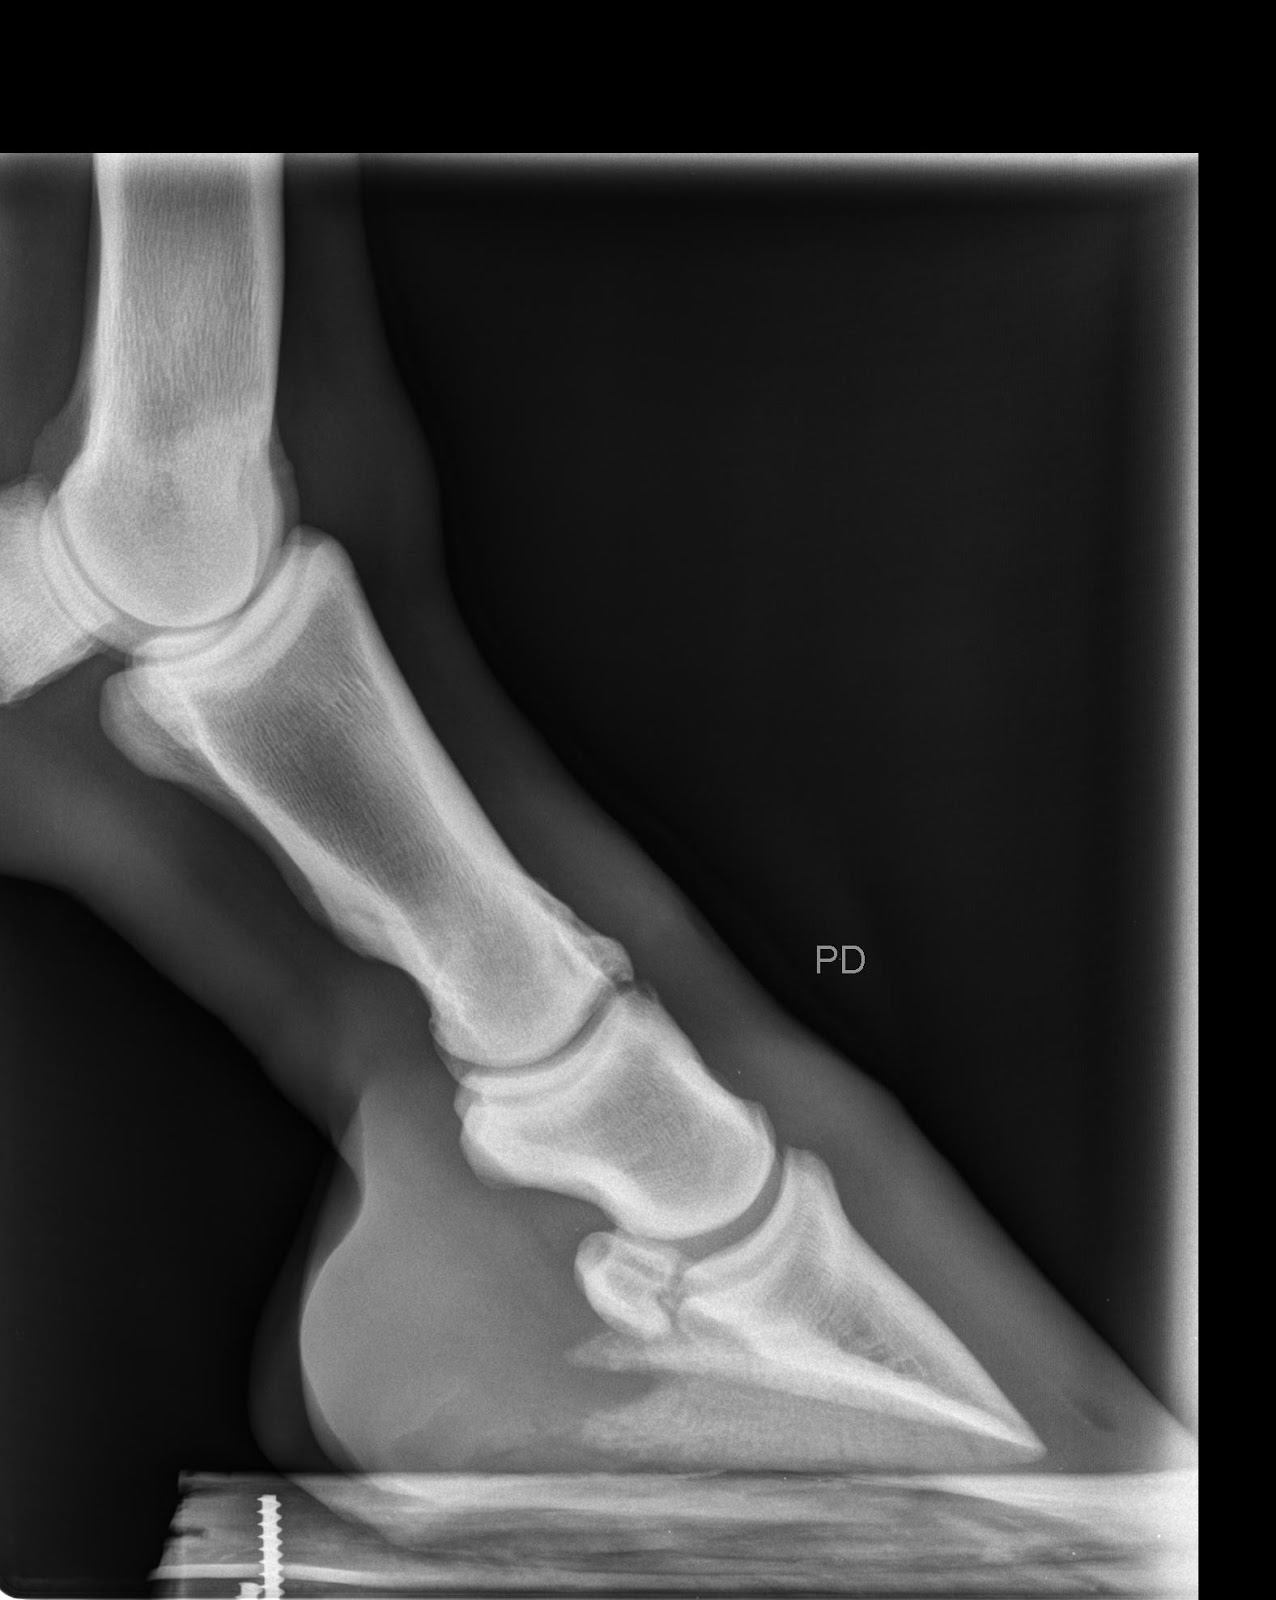

Tamtam was next. The key with Tamtam is providing sufficient support for his collapsed heels. Eric has very good feet and strong heels so he doesn't have this problem.You can see the collapsed heels very clearly on this photo taken before he was shod:

Here is one of Tamtam's front feet with the new shoe in place:

You can clearly see the support for the collapsed heels.